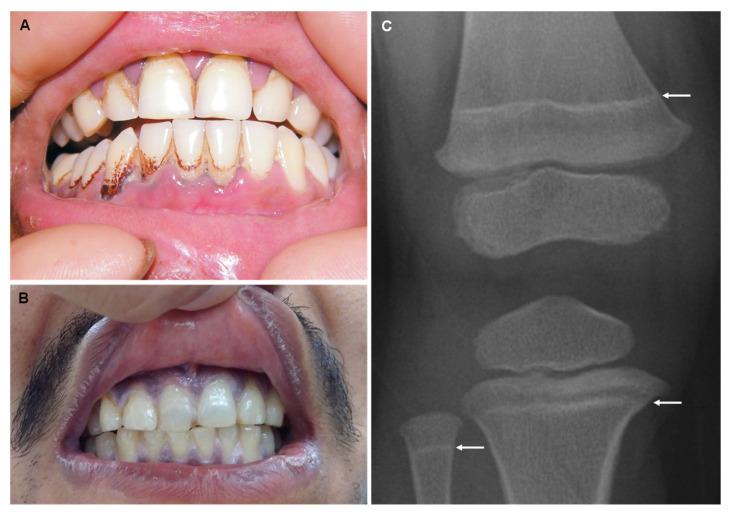

Several heavy metals and other chemical elements are natural components of the Earth's crust and their properties and toxicity have been recognized for thousands of years. Moreover, their use in industries presents a major source of environmental and occupational pollution. Therefore, this ubiquity in daily life may result in several potential exposures coming from natural sources (e.g., through food and water contamination), industrial processes, and commercial products, among others. The toxicity of most chemical elements of the periodic table accrues from their highly reactive nature, resulting in the formation of complexes with intracellular compounds that impair cellular pathways, leading to dysfunction, necrosis, and apoptosis. Nervous, gastrointestinal, hematopoietic, renal, and dermatological systems are the main targets. This manuscript aims to collect the clinical and forensic signs related to poisoning from heavy metals, such as thallium, lead, copper, mercury, iron, cadmium, and bismuth, as well as other chemical elements such as arsenic, selenium, and fluorine. Furthermore, their main sources of occupational and environmental exposure are highlighted in this review. The importance of rapid recognition is related to the fact that, through a high degree of suspicion, the clinician could rapidly initiate treatment even before the toxicological results are available, which can make a huge difference in these patients' outcomes.

几种重金属和其他化学元素是地壳的天然组成部分,它们的性质和毒性在数千年前就已被认识到。此外,它们在工业中的使用是环境和职业污染的一个主要来源。因此,它们在日常生活中的这种普遍存在可能导致来自自然来源(例如,通过食物和水污染)、工业过程以及商业产品等的多种潜在暴露。元素周期表中大多数化学元素的毒性源于它们的高反应活性,导致与细胞内化合物形成复合物,从而损害细胞通路,进而导致功能障碍、坏死和凋亡。神经、胃肠、造血、肾脏和皮肤系统是主要的靶器官。本手稿旨在收集与铊、铅、铜、汞、铁、镉和铋等重金属中毒以及砷、硒和氟等其他化学元素中毒相关的临床和法医体征。此外,本综述还强调了它们职业和环境暴露的主要来源。快速识别的重要性在于,通过高度怀疑,临床医生甚至可以在毒理学结果出来之前就迅速开始治疗,这对这些患者的预后可能会产生巨大影响。